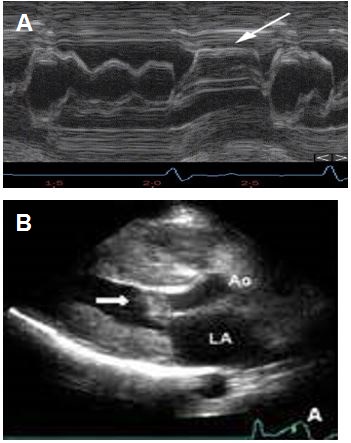

Imaging In Hypertrophic Cardiomyopathy - American College Of Cardiology

Imaging in Hypertrophic Cardiomyopathy - American College of Cardiology www.acc.org

hypertrophic cardiomyopathy imaging cardiology mitral valve figure mode sam